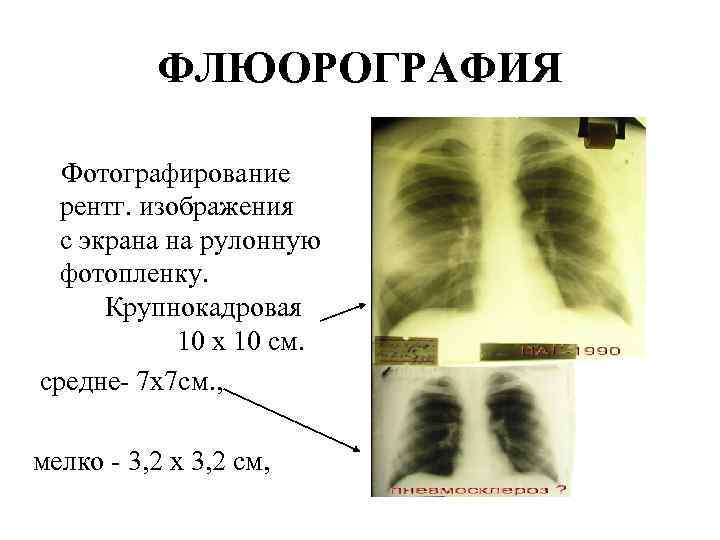

Фотографии рентгеновских снимков без необходимости направления от врача